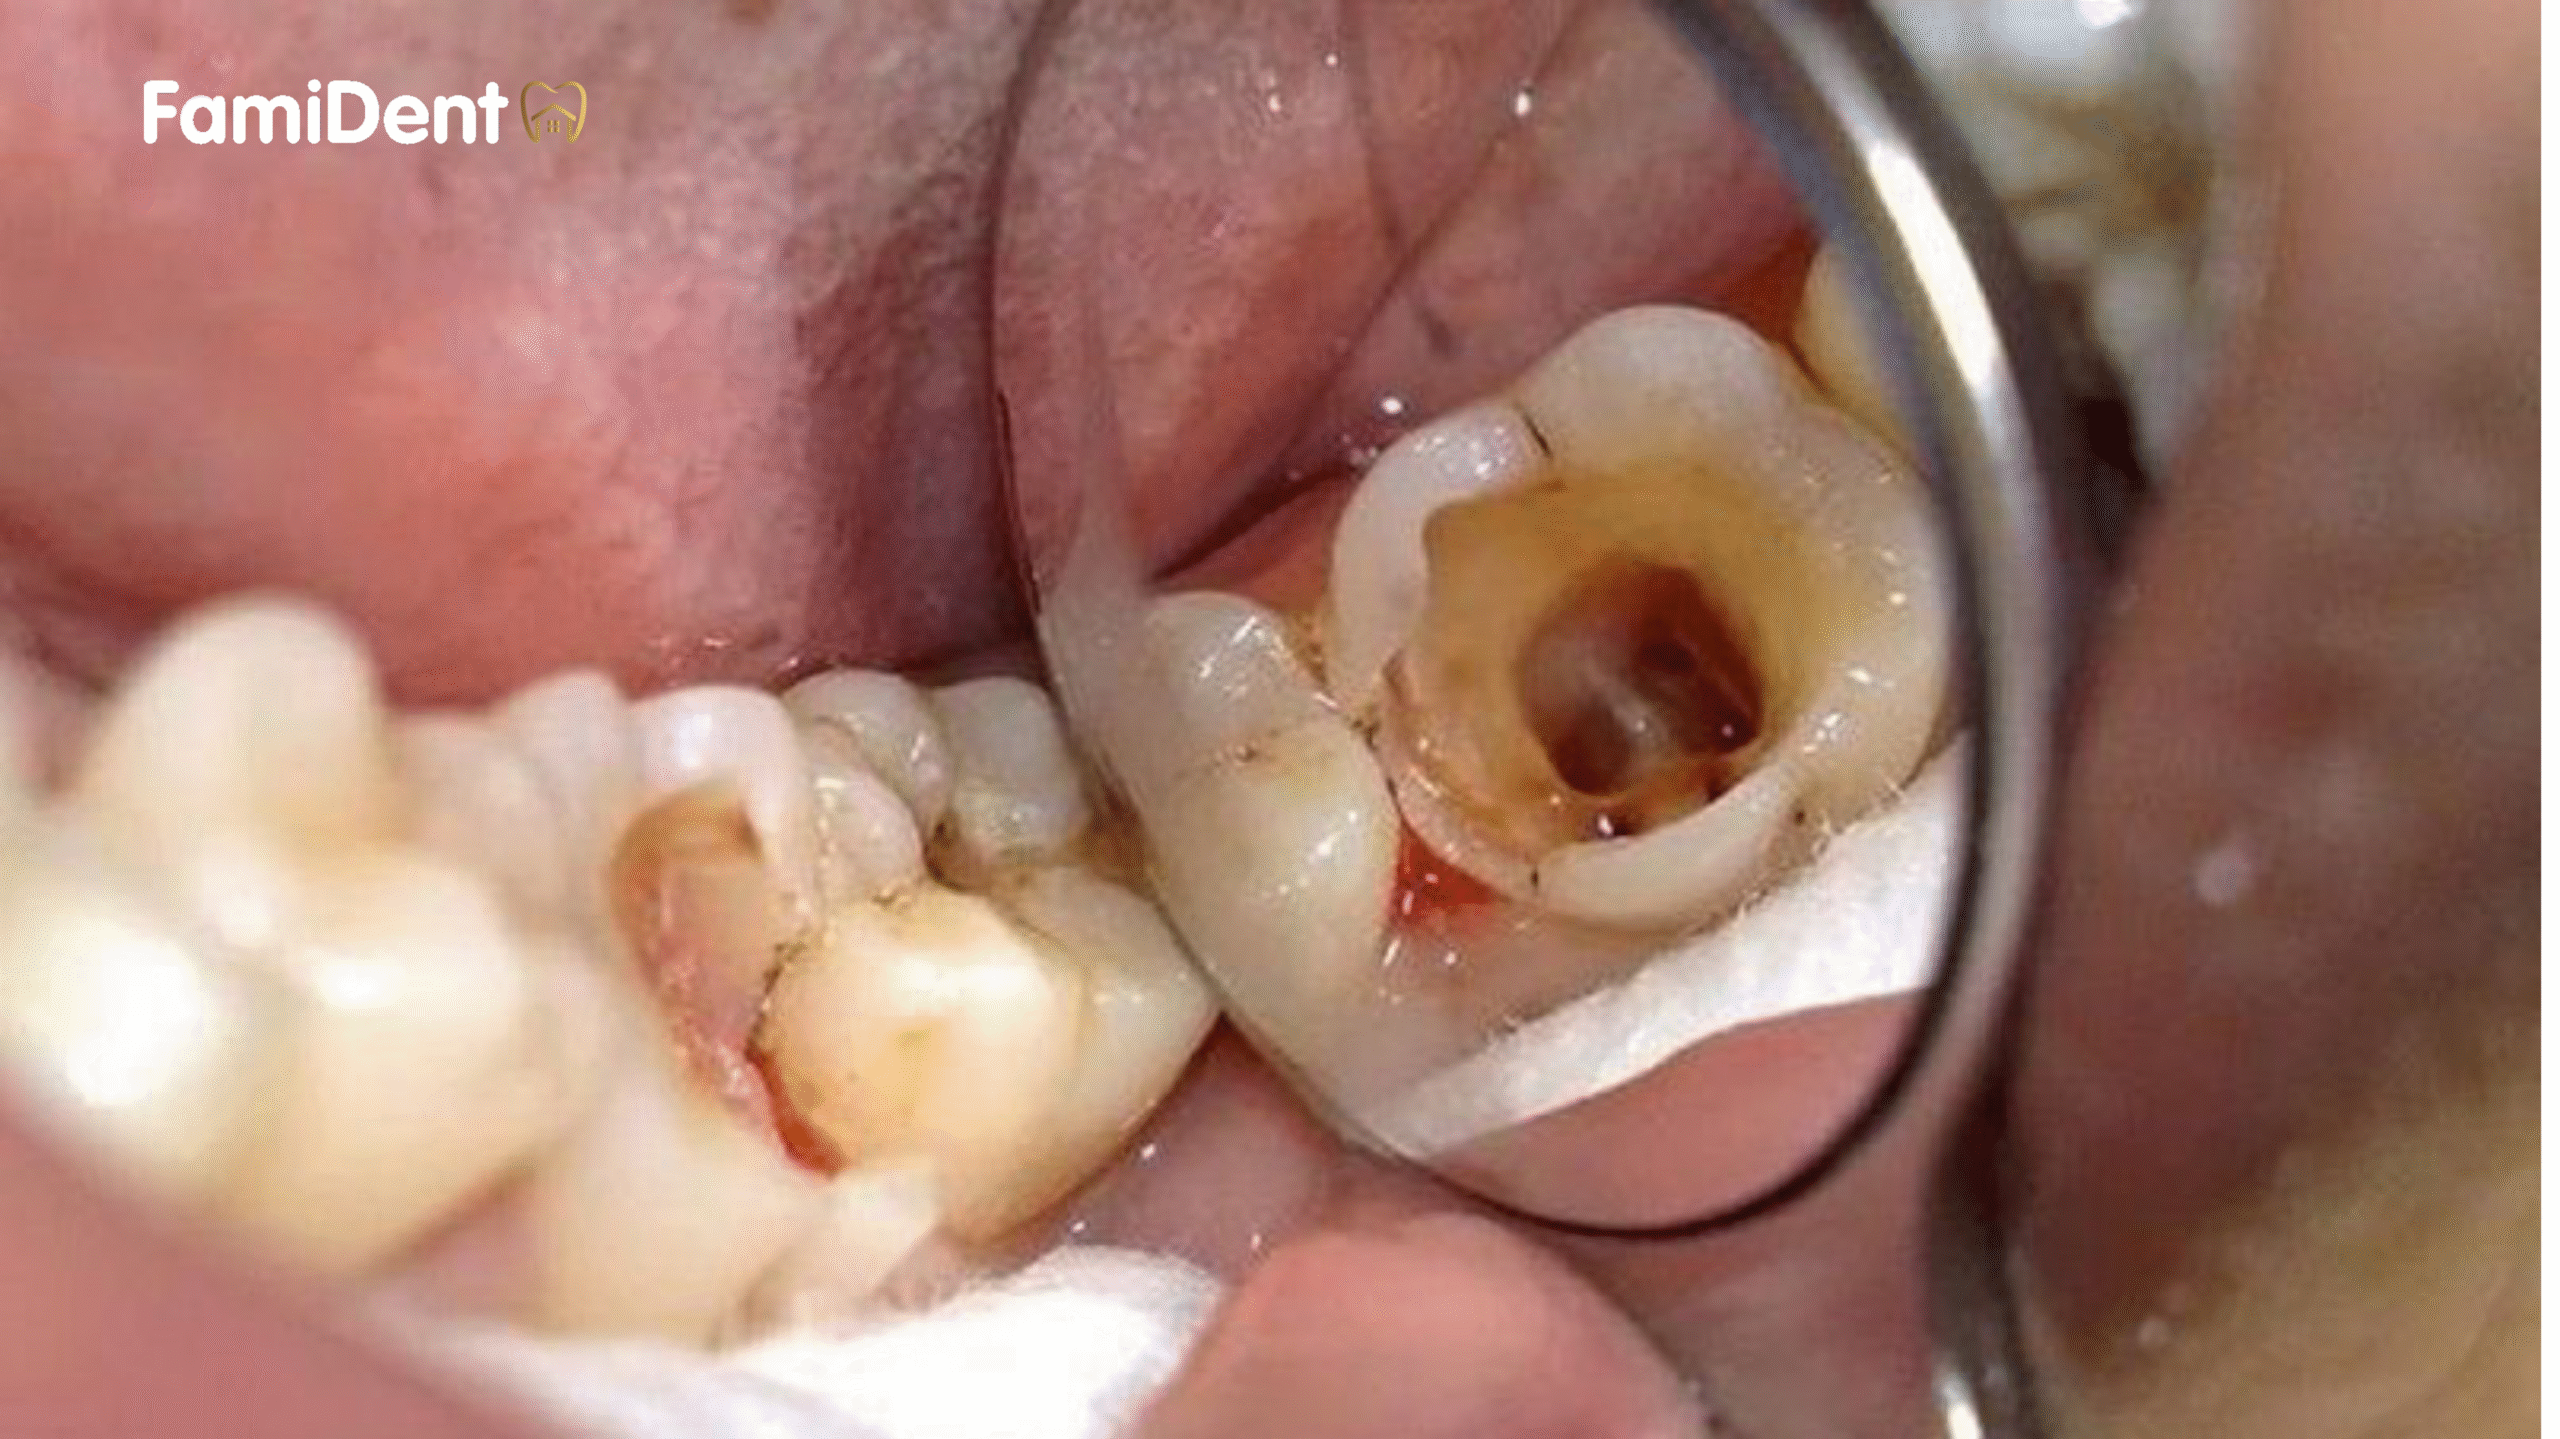

- Sâu răng nặng: Sâu răng ăn sâu vào tủy, gây viêm hoặc nhiễm trùng tủy răng.

- Viêm tủy không hồi phục: Tủy răng bị viêm nặng, gây đau nhức kéo dài, không thể tự phục hồi.

Nếu bạn gặp các triệu chứng như đau nhức dữ dội, sưng nướu, hoặc răng đổi màu, hãy đến nha khoa ngay để được kiểm tra và điều trị kịp thời.

- Thăm khám và chẩn đoán: Bác sĩ kiểm tra tình trạng răng bằng khám lâm sàng và chụp X-quang để xác định mức độ tổn thương tủy.